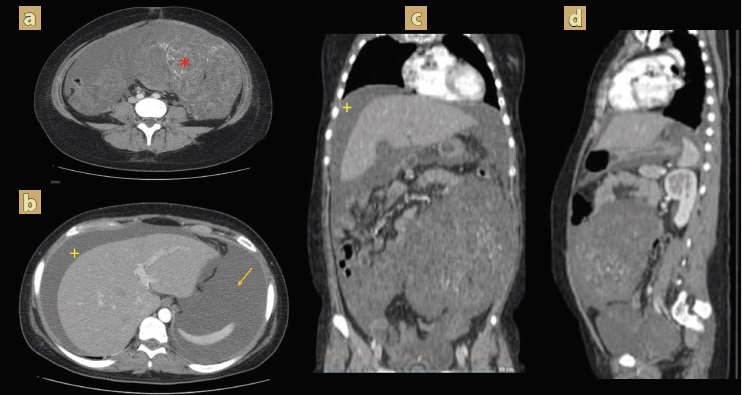

A los 3 meses del postquirúrgico inició con incremento del perímetro abdominal, se realizó tomografía abdominal contrastada de control, evidenciándose persistencia de la enfermedad a nivel retroperitoneal, así como tumor que abarcaba toda la pelvis, derrame pleural bilateral y ascitis (figura 1); reporte de resultados de laboratorio con hormona gonadotropina coriónica humana fracción beta negativa y alfafetoproteína negativa (tabla 1), por lo cual se indicó comenzar manejo con 3 ciclos de quimioterapia y posteriormente se le realizó una laparotomía exploratoria en la que realizaron la resección de tumoraciones intraabodminales con reporte de patología con teratoma maduro en las 3 muestras tomadas. En seguimiento con oncología y tomografía abdominal de control, hubo evidencia de aparición de tumoración hepática (figura 2) sugerente de actividad metastásica, por lo que requirió un nuevo procedimiento quirúrgico y se realizó la intervención con evidencia de tumoración que ocupa la cara posterior y superior del hígado en segmentos VI y VII, así como dos tumoraciones a nivel del retroperitoneo; se realizó la resección de estas, todas con reporte histopatológico de teratoma quístico maduro sin evidencia de neuroepitelio.

Figura 1 Tomografía abdominopélvica contrastada postoperatoria a y b) cortes axiales c y d (reformateo coronal y sagital) con presencia de una tumoración sólida, heterogénea, con realce al medio de contraste que abarca toda la pelvis asociado a siembra de metástasis peritoneales, con pérdida de interface grasa con la vejiga (*), derrame pleural bilateral (+) y ascitis (flecha).